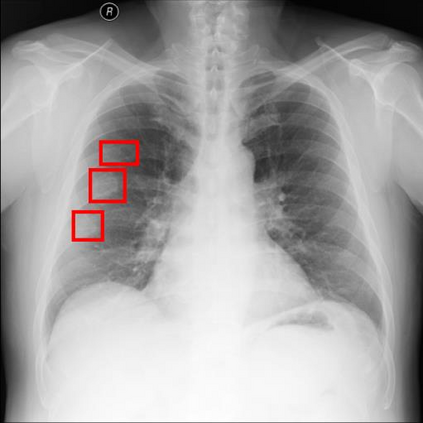

Chest X-ray (CXR) is the most typical diagnostic X-ray examination for screening various thoracic diseases. Automatically localizing lesions from CXR is promising for alleviating radiologists' reading burden. However, CXR datasets are often with massive image-level annotations and scarce lesion-level annotations, and more often, without annotations. Thus far, unifying different supervision granularities to develop thoracic disease detection algorithms has not been comprehensively addressed. In this paper, we present OXnet, the first deep omni-supervised thoracic disease detection network to our best knowledge that uses as much available supervision as possible for CXR diagnosis. We first introduce supervised learning via a one-stage detection model. Then, we inject a global classification head to the detection model and propose dual attention alignment to guide the global gradient to the local detection branch, which enables learning lesion detection from image-level annotations. We also impose intra-class compactness and inter-class separability with global prototype alignment to further enhance the global information learning. Moreover, we leverage a soft focal loss to distill the soft pseudo-labels of unlabeled data generated by a teacher model. Extensive experiments on a large-scale chest X-ray dataset show the proposed OXnet outperforms competitive methods with significant margins. Further, we investigate omni-supervision under various annotation granularities and corroborate OXnet is a promising choice to mitigate the plight of annotation shortage for medical image diagnosis.